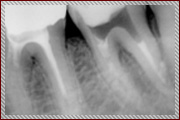

上記は歯のレントゲン写真です。二本足のように、歯が歯茎に埋まってますが、右の歯の黒い部分(二本足のつけ根の部分)が菌に冒されてます。

-

非常に細かい部分ですが、顕微鏡を使い、菌に犯されているところを治療した後にレントゲンを取りました。

しっかり治ってます!!